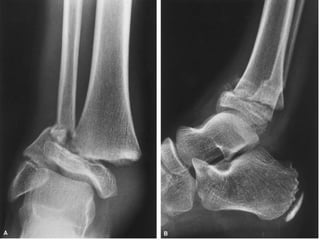

DIAGNOSTICO Clínico Radiológico  2 proyecciones o mas

ESTUDIOS RADIOGRAFICOS SIMPLES Corroboran la presencia de Fx. Permiten darse cuenta de la lesión de partes blandas La localización de la Fx. Tipo de trazos de la Fx. Numero de fragmentos El desplazamiento La presencia o ausencia de una patología

LOCALIZACION Diafisiaria Metafisiaria Epifisiaria Intraarticular Fractura-luxación